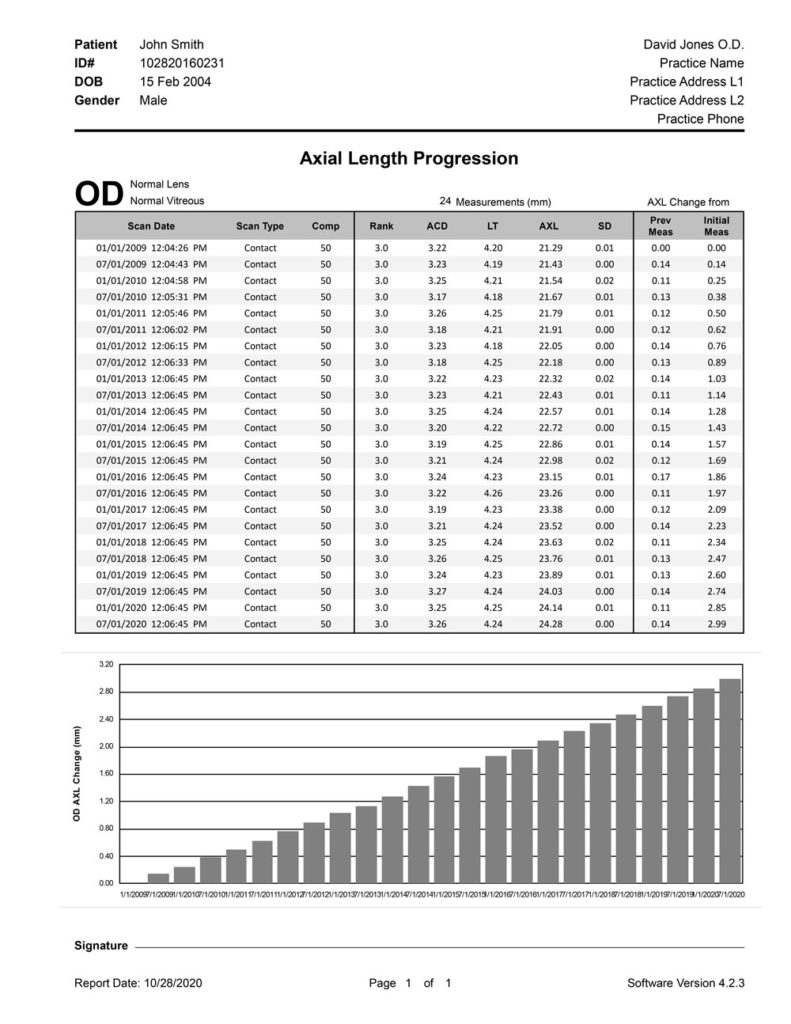

MONITORING AXIAL LENGTH PROGRESSION

The Flex A-Scan is tailored to meet the needs of your myopia management program. In addition to providing consistent, accurate and reliable axial length measurements, the Axial Length Progression Report charts the axial length changes of each patient over a period of time.